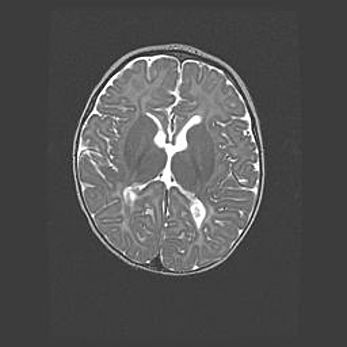

Церебральная ишемия II.

Возраст: 5 дней

Вес: 3400 г

Пол: женский

Окружность головы: 35 см

Срок гестации: 39 недель

Церебральная ишемия – это заболевание, характеризующееся недостаточностью (гипоксией) либо полным прекращением (аноксией) снабжения мозга кислородом по причине закупорки одного или нескольких сосудов. Это приводит к  что метаболическим расстройствам различной степени тяжести в тканях головного мозга, развитию коагуляционных некрозов и гибели нейронов.